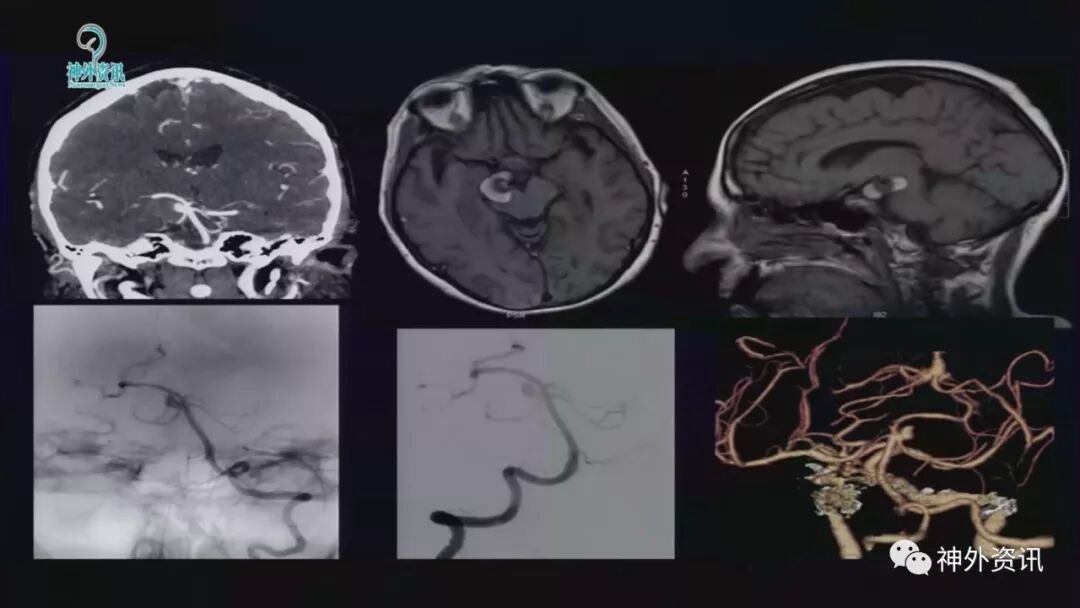

巨大的复杂动脉瘤,常规介入治疗的复发率较高,而目前的血流转向装置也具有治疗后再出血的不确定性。因此,手术治疗仍然在此类疾病中占有重要的地位。但由于相比介入操作而言,手术的难度更大、技术要求更高,也使得许多神经外科医生望而却步。Lawton教授是当今国际上享有盛誉的脑血管病大师,他专注于脑血管病的手术治疗,目前已夹闭各类脑动脉瘤4400余例。除了丰富的临床经验,他非常善于总结,能够将复杂的疾病解剖知识和手术操作要点通俗而又详细的在其著作中表现出来。本期回顾的是Lawton教授所做的关于复杂脑动脉瘤的手术治疗的报告,希望对有志于从事此类挑战性工作的神经外科医师们有所帮助。